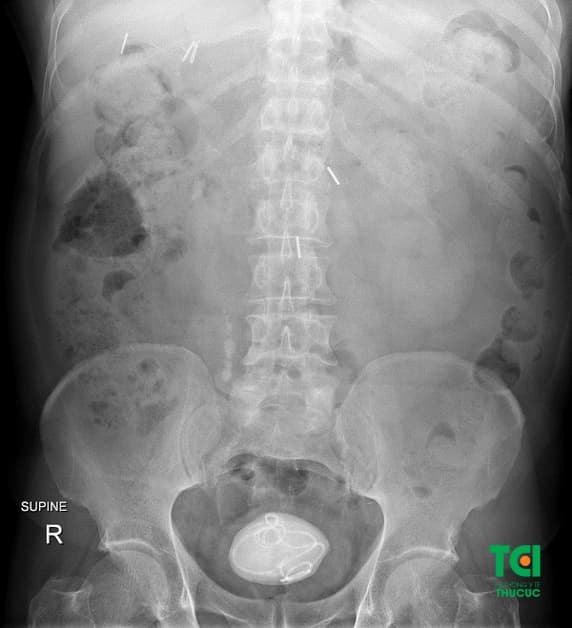

Khi chụp XQ thận thường, hình ảnh sỏi bàng quang cản quang thường hình tròn, có nhiều vòng đồng tâm trong vùng tiểu khung, trên khớp mu.

Hình ảnh sỏi bàng quang khi chụp x quang thận thường